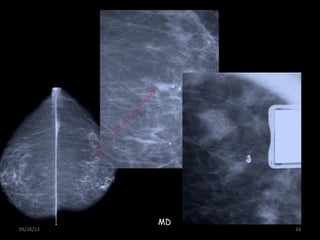

MD

05/26/13 24

05/26/13 23 Inc. Compl.:MAGNIFICACION  Solo se magnifican MICROCALCIFICACIONES  NO bucky  Usar colimador y foco fino  Grado de inclinación: igual al usado en cada incidencia MD

• 24.